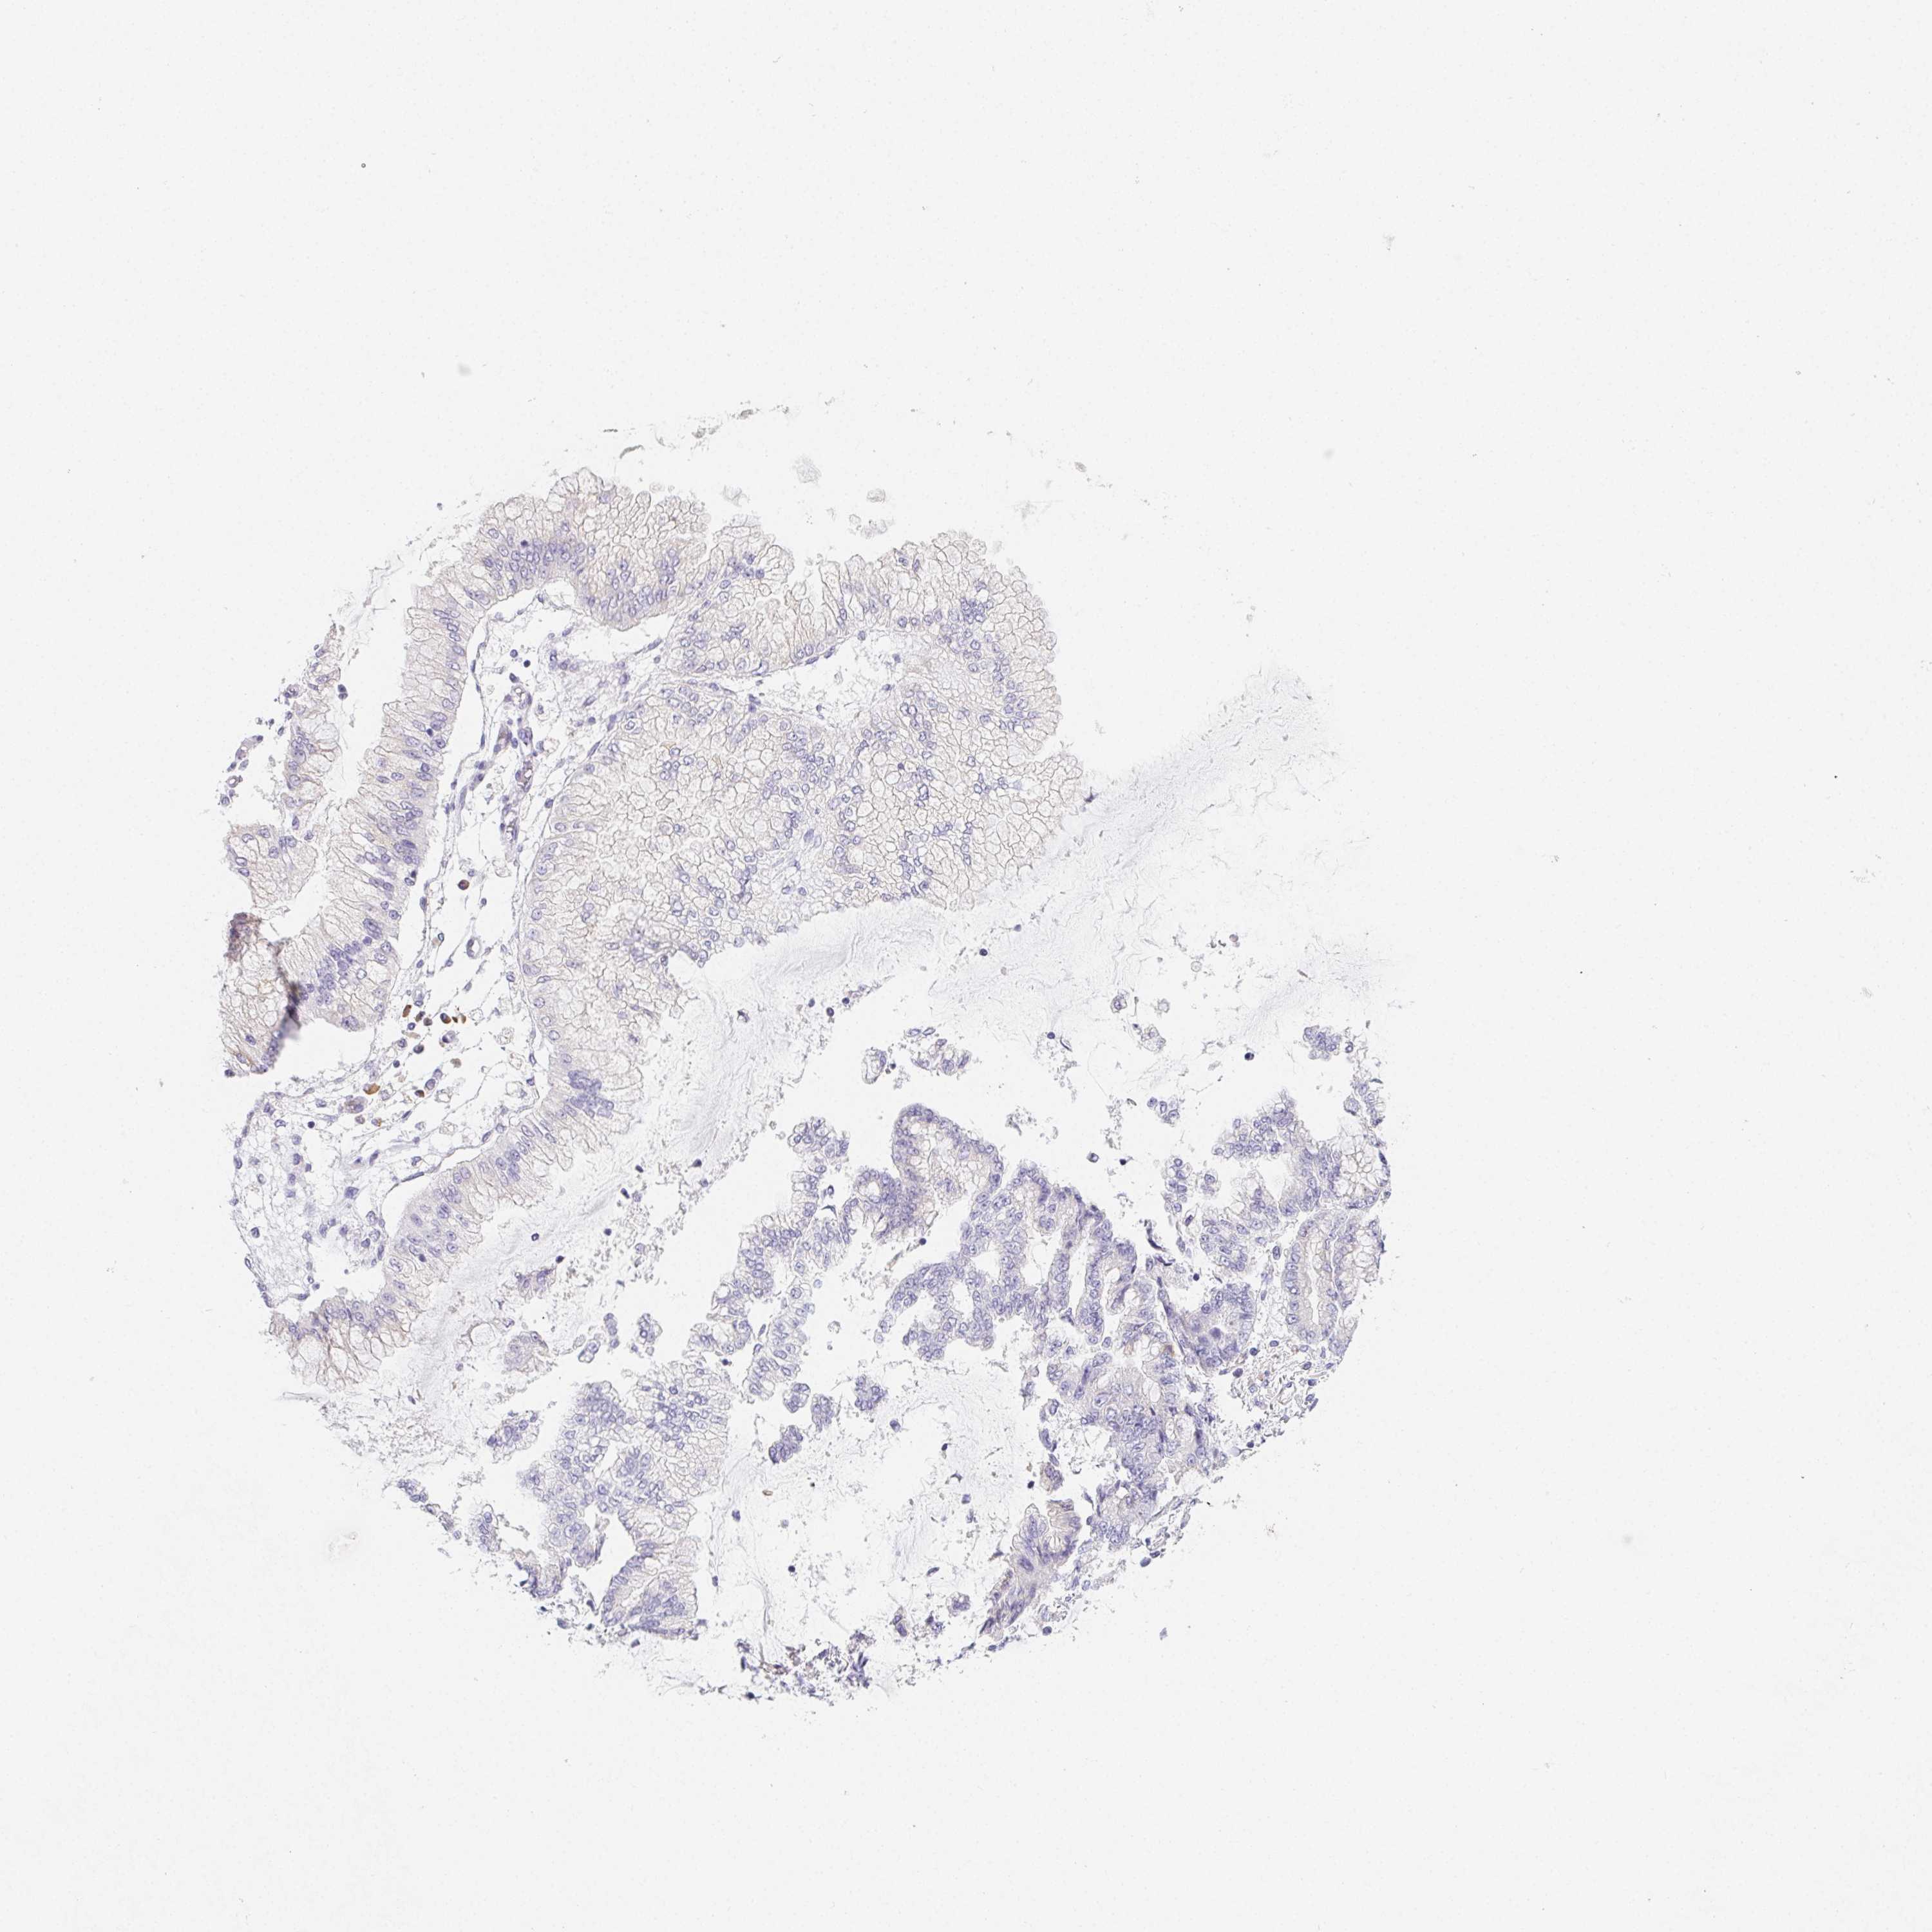

STOMACH CANCER - Protein expressioni

A mouse-over function shows sample information and annotation data. Click on an image to view it in a full screen mode. Samples can be filtered based on level of antibody staining by selecting one or several of the following categories: high, medium, low and not detected. The assay and annotation is described here.

Antibody stainingi

Antibody staining in the annotated cell types in the current human tissue is reported as not detected, low, medium, or high, based on conventional immunohistochemistry profiling in selected tissues. This score is based on the combination of the staining intensity and fraction of stained cells.

Each image is clickable and will lead to virtual microscopy that enables deeper exploration of all samples and also displays staining intensity scores, fraction scores and subcellular localization as well as patient and tissue information for each sample.

Antibody HPA004833

Staining

High

Medium

Low

Not detected

Intensity

Strong

Moderate

Weak

Negative

Quantity

>75%

75%-25%

<25%

None

Location

Nuclear

Cytoplasmic/membranous

Cytoplasmic/membranous,nuclear

Adenocarcinoma, NOS